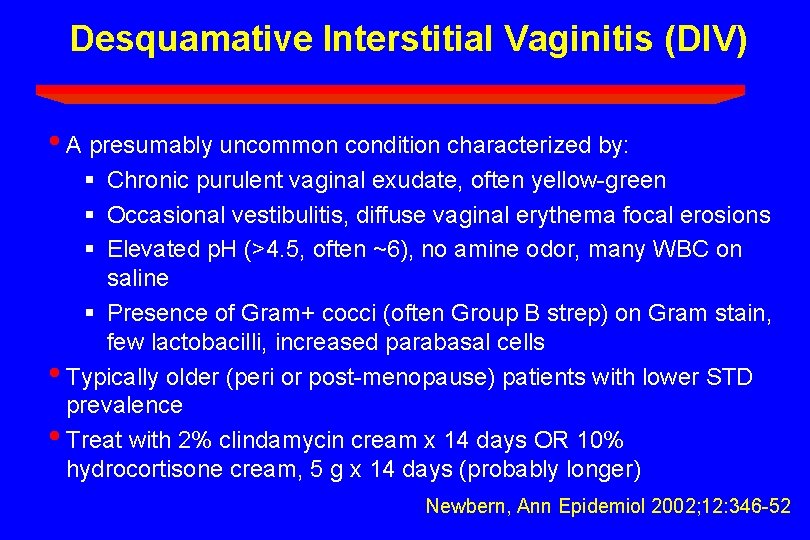

Desquamative Interstitial Vaginitis (DIV) • A presumably uncommon condition characterized by: § Chronic purulent vaginal exudate, often yellow-green § Occasional vestibulitis, diffuse vaginal erythema focal erosions § Elevated p. H (>4. 5, often ~6), no amine odor, many WBC on saline § Presence of Gram+ cocci (often Group B strep) on Gram stain, few lactobacilli, increased parabasal cells • Typically older (peri or post-menopause) patients with lower STD prevalence • Treat with 2% clindamycin cream x 14 days OR 10% hydrocortisone cream, 5 g x 14 days (probably longer) Newbern, Ann Epidemiol 2002; 12: 346 -52